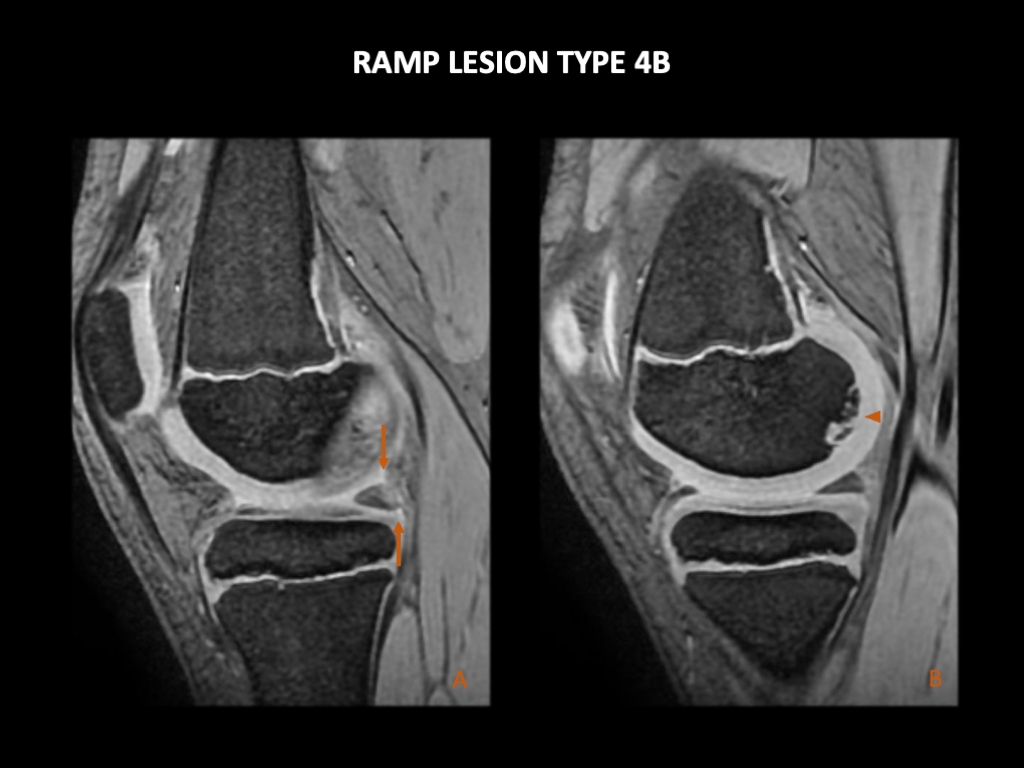

图 21:一名10岁女性在外伤后膝痛,出现Ramp损伤类型4B。左膝3T MRI:(A) 矢状GRE图像显示内侧半月板后角的半月板关节囊韧带和半月板胫骨韧带断裂。这与Thaunat类型4和Greif类型4B的Ramp损伤一致。(B) 矢状GRE显示内侧股骨髁后部的骨软骨损伤。还有明显的关节积液。